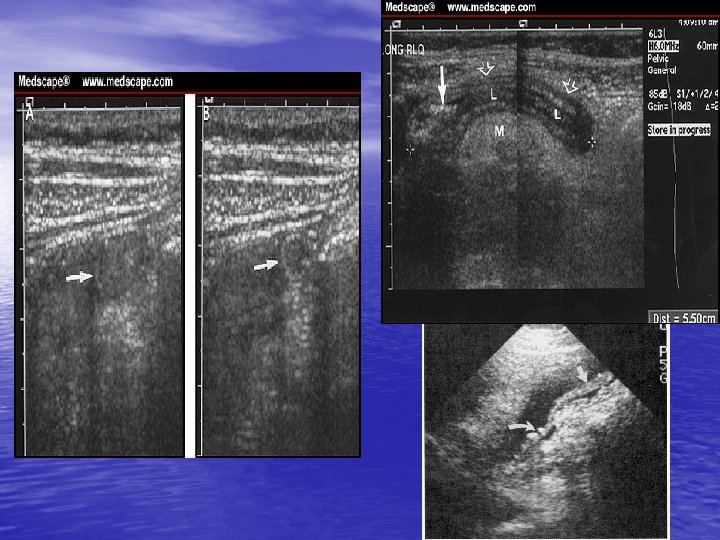

USG ü Colecţii lichidiene (exactitatea este de 92, 8% în determinarea abceselor) ü Determinarea dimensiunilor: organelor parinchimatoase calculilor biliari, pielocaliceali, ureterali căilor biliare intra şi extrahepatice ductului Wirsung, etc.